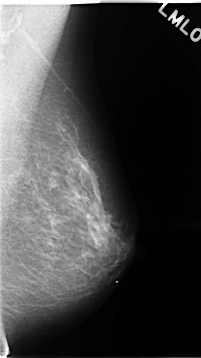

C_0110_1.RIGHT_CC

LEFT_MLO LINES 4648 PIXELS_PER_LINE 2608 BITS_PER_PIXEL 12 RESOLUTION 50 NON_OVERLAY